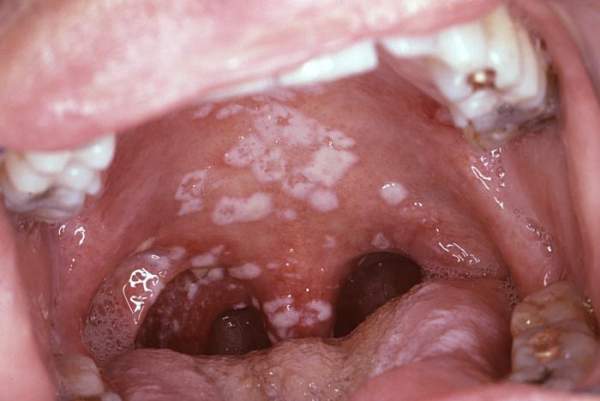

Najpoznatija vrsta je Candida albicans (u prijevodu: “bijela kandida”). Voli topla, vlažna, tamna mjesta – poput usne šupljine, probavnog trakta, rodnice, kože, noktiju… Iako je prirodno prisutna u tijelu, pod određenim uvjetima može se prekomjerno razmnožiti i izazvati kandidijazu – stanje koje uključuje različite gljivične infekcije.

oralna kandidijaza (bijele naslage u ustima, osjećaj pečenja)

oralna kandidijaza (soor),

Najčešći oblik je Candida albicans, koja u manjim količinama živi u usnoj šupljini. No, pod određenim uvjetima – buja.

- bijeli, sirasti sloj na jeziku i sluznici